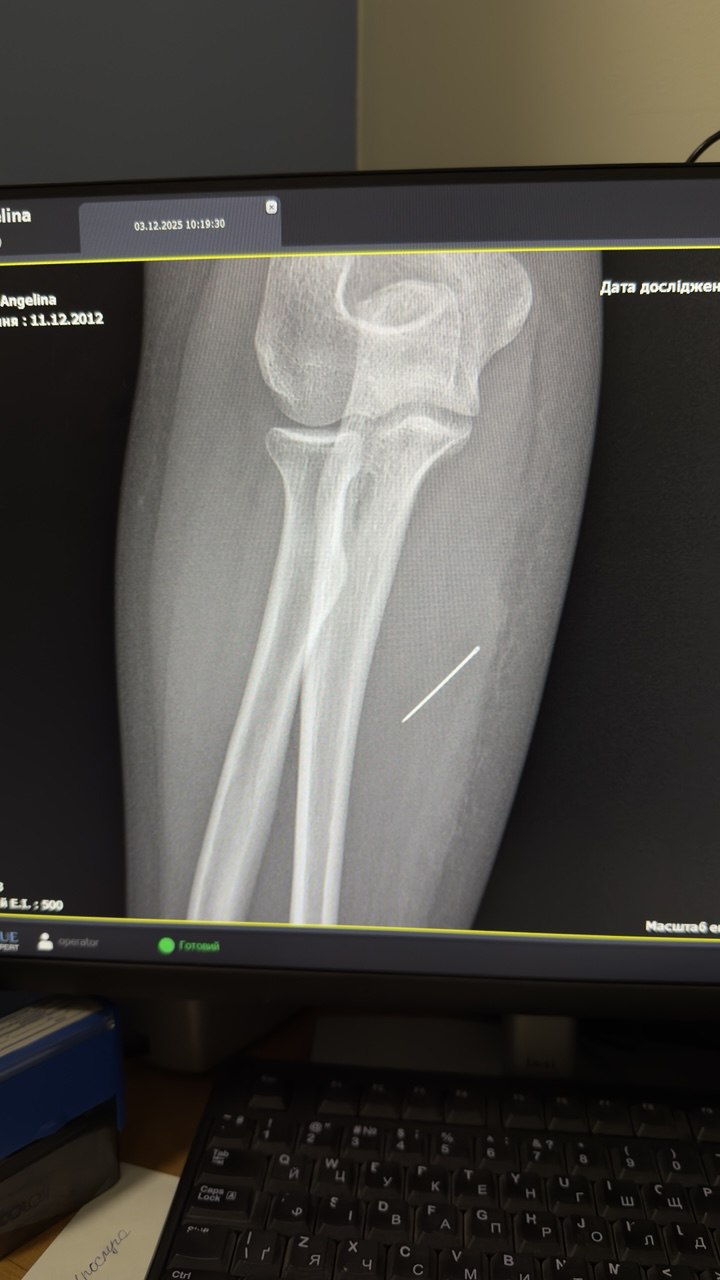

Під час огляду лікарі запідозрили сторонній предмет і направили дитину на УЗД м’яких тканин, де й виявили голку. Згодом рентген підтвердив, що вона зайшла під кутом 45 градусів і застрягла глибоко в товщі м’яза, продовжуючи мігрувати всередині тіла.

Під час операції лікарям було критично важливо витягнути голку точно за траєкторією її входження, аби вона не зламалася. За допомогою рентген-навігації ЕОП хірурги точно визначили місце стороннього тіла, виконали невеликий розріз і безпечно його видалили.